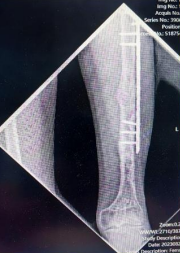

患者左股骨与胫骨骨折术后X光检查结果

说起李先生的病情,还要追溯到九年前的一场意外。在那场意外中,李先生左股骨与胫骨严重骨折,虽然在当地医院接受了手术治疗,但术后李先生小腿逐渐短缩畸形。这一变化不仅限制了他的日常活动,更是让他的生活笼罩在一层无形的阴影之中,极大地损害了心理健康。